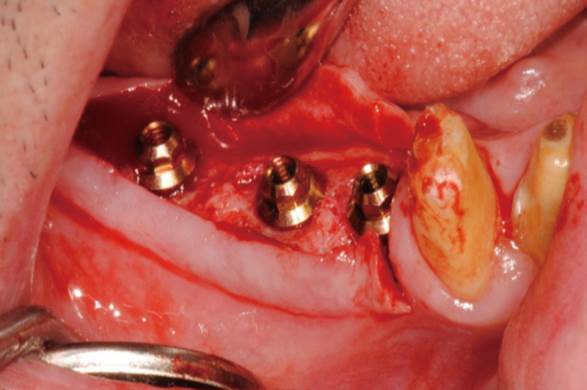

Clinical case: Extraction of all teeth in upper maxilla,

immediate implant placement, & provisionalization

- Courtesy of Dr. Iulian Filipov, Romania -